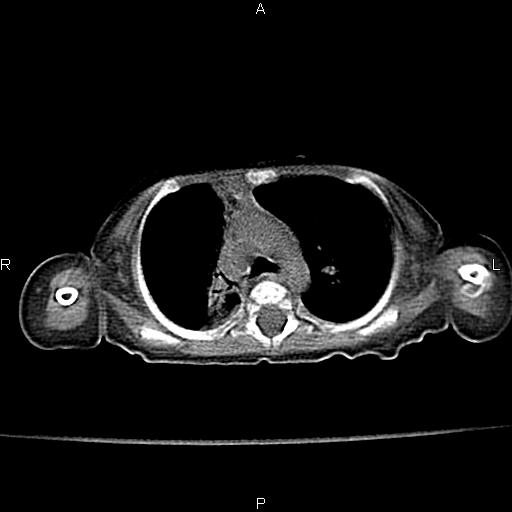

以下是引用aa13877358820在2010-7-26 12:35:00的发言:[br]男性,三个月,卧位胸片,咳嗽、气促、发热14天,两肺闻及细小水泡音。[br]